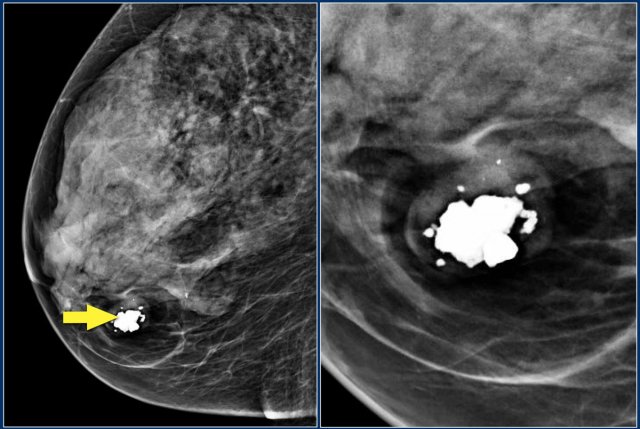

The images show a fat-containing lesion with a popcorn-like calcification.

All fat-containing lesions are typically benign.

These image-findings are diagnostic for a hamartoma - also known as fibroadenolipoma.